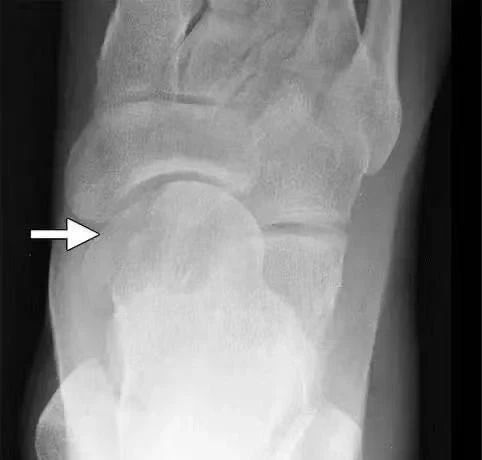

(7)踝部骨折脱位

距骨骨折脱位:多由高处跌下所致,压痛点在距骨,X线片可协助鉴别。

踝部韧带损伤:多由踝关节扭伤所致,肿痛,压痛点在内踝下方或外踝的前下或下方,无骨擦音和畸形;X线摄片可排除骨折。